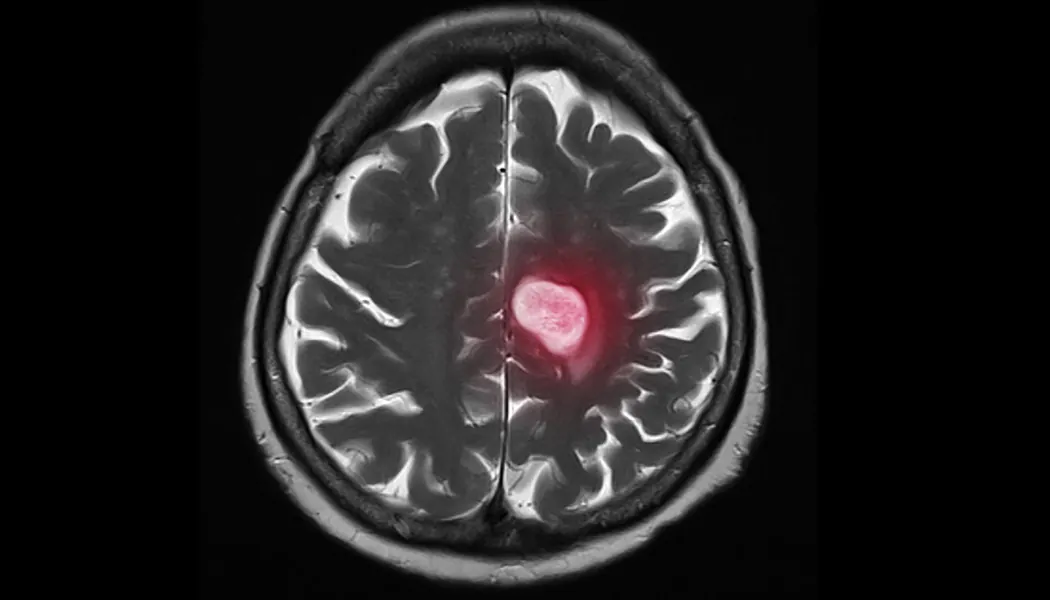

Brain metastases occur in about 10% of all patients with cancer and in as many as a third of women with advanced metastatic breast cancer. Though experts have made great strides in suppressing the spread of cancer, there is still little known about the cellular pathways that enable cancer cells to selectively grow in the brain; that is, until Dr. Haber and his research team identified a signaling pathway that appeared significantly more active in brain metastases from breast cancer.

The research commenced approximately 10 years ago while investigating circulating tumor cells (CTCs). As their research progressed, the team homed in on a specific signaling pathway named HIF1A. Using cells from women with breast cancer, the team observed how these cells acted in animal models. It was discovered that if HIF1A was suppressed, the rate of proliferation (or rapid growth) was reduced. Simply put, blocking the HIF1A signaling pathway could reduce the rate of brain metastasis or even prevent it altogether.

“HIF1A is not specific to brain metastasis, since it’s a very broadly activated pathway in many cancers,” Dr. Haber began. “However, it appears to be more active in brain metastases from breast cancer than in primary breast cancers, and that may help explain what makes these metastases to the brain so unique and so difficult to treat.”

The pathway identified in this research is already well known in the cancer world, however its special relevance to the brain was not known until now. Theoretically, a drug could be developed to suppress HIF1A and, in turn, prevent the spread of cancer. While a very promising discovery, Dr. Haber explains that there is far more work to be done.